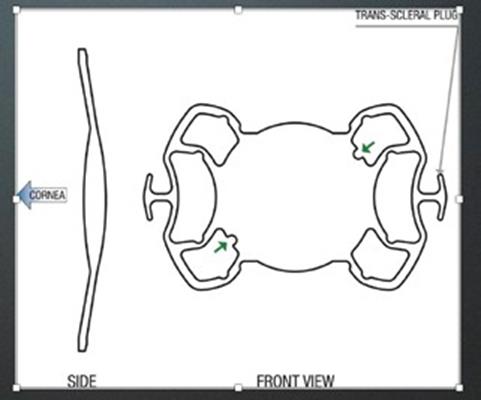

Ο ενδοφακός αυτός έχει στα δυο haptics του άγκυρες, σχήματος Τ, που επιτρέπουν τη στήριξη του ενδοφακού στον σκληρό χωρίς τη χρήση ραμμάτων, διασφαλίζοντας τη σταθερότητά του. Εκατέρωθεν των αγκυρών έχει δύο πτερύγια (flaps), που περιορίζουν την πιθανότητα κλίσης και μερικής στροφής (tilting) του φακού. Παράλληλα, το οπτικό μέρος του φακού είναι μεγάλο, 6,5mm, προσφέροντας κατάλληλη λύση ακόμα και σε περιστατικά με ανιριδία ή παραμορφωμένη κόρη, χωρίς να δημιουργεί φαινόμενα παράθλασης ή εκτροπών. Ιδιαίτερα σε περιστατικά με ανιριδία προσφέρει ελάττωση της φωτοφοβίας. Αυτό συμβαίνει διότι τα πτερύγια και τα εξαρτήματα του ενδοφακού εκατέρωθεν του οπτικού τμήματος σκεδάζουν το φως προς την περιφέρεια προστατεύοντας τον οπίσθιο πόλο από την υπερβολική έκθεση στο φως. Τέλος, το οπτικό μέρος του ενδοφακού έχει μια οπίσθια κλίση 10° που αποτρέπει την ανάπτυξη μετεγχειρητικά κορικού αποκλεισμού. Λόγω της σταθερότητας που προσφέρει ο Carlevale ενδοφακός, στο τέλος της επέμβασης μπορεί να γίνει έλεγχος της περιφέρειας του αμφιβληστροειδούς μέσω σκληρικής πίεσης, για την εύρεση και θεραπεία πιθανών ρήξεων αμφιβληστροειδούς που θα μπορούσαν να οδηγήσουν μετέπειτα σε αποκόλληση. Ως εκ τούτου οι μετεγχειρητικές επιπλοκές έχουν ελαχιστοποιηθεί, συγκριτικά με τη χρήση μη ενδεδειγμένων ενδοφακών για σκληρική στήριξη.

Η τεχνική ένθεσης του ενδοφακού απαιτεί διάνοιξη του επιπεφυκότα, δημιουργία σκληρικών κρημνών στις θέσεις 3 και 9 ώρα. Κατόπιν πρέπει να αφαιρεθεί ο παρεκτοπισμένος ενδοφακός ή τα υπολείμματα του κρυσταλλικού φακού που έμειναν μέσα κατά τη διάρκεια της επιπλεγμένης προηγηθείσας επέμβασης του καταρράκτη. Στη συνέχεια, αν υπάρχει δυνατότητα για ολική υαλοειδεκτομή (χειρουργός οπισθίου ημιμορίου και μηχάνημα με αντίστοιχο μικροσκόπιο), θα είναι προτιμητέο αυτό να γίνει. Αν όχι, τότε ο χειρουργός του πρόσθιου ημιμορίου θα πρέπει να κάνει μία εντεταμένη πρόσθια υαλοειδεκτομή. Και στις δυο περιπτώσεις η ολική ή η μερική αφαίρεση του υαλοειδούς θα ελαττώσει τις πιθανές μετεγχειρητικές ήπιες (μυωψίες, φωταψίες) ή σοβαρές (φλεγμονές, κυστικό οίδημα ωχράς, αποκόλληση του αμφιβληστροειδούς) επιπλοκές.

Κατόπιν από μία κερατική τομή των 2,75 χιλ ενθέτεται ο ενδοφακός. Απαιτείται ένα ειδικό ζεύγος λαβίδων για να μην τραυματισθούν ή αποσπασθούν οι άγκυρες του ενδοφακού κατά τη διαδικασία εξωτερίκευσής τους από τον σκληρό χιτώνα. Οι γνωστές λαβίδες του αμφιβληστροειδούς (serrated ή end- griping) συχνά τραυματίζουν ή ακόμη αποκόπτουν εντελώς την άγκυρα από το σώμα του φακού εάν ασκηθεί υπερβολική πίεση στης λαβές της λαβίδας. Υπάρχουν όμως και οι ειδικά κατασκευασμένες γι’ αυτό τον λόγο λαβίδες (Shariot και Carlevale) που έχουν μαλακές και ευαίσθητες ατραυματικές σιαγόνες. Αυτές είναι οι κατάλληλες για την τοποθέτηση του ενδοφακού. Ο φακός έχει εγκοπές στην άκρη του οπτικού του μέρους που υποδεικνύουν τη σωστή θέση του μέσα στον οπ. θάλαμο (κοίλο μέρος προς τα εμπρός). Έτσι εμποδίζεται η επαφή του φακού με το κορικό χείλος και αποτρέπεται ο κορικός αποκλεισμός και η αύξηση της ενδοφθάλμιας πίεσης. Επίσης, αποφεύγεται η επαφή και ο χρόνιος ερεθισμός της ίριδας με ό,τι αυτό συνεπάγεται.

Οι σκληρικοί κρημνοί ήταν η αρχική τεχνική που συνόδευε την τοποθέτηση του ενδοφακού. Στη συνέχεια ακολούθησε η τεχνική την κάθετων τομών στο ΣΚΟ και οι δημιουργία θυλάκων (τσέπες) εκατέρωθεν της τομής. Μέσα σε αυτούς τους θυλάκους τοποθετούνται οι προεξοχές (αυτιά) της άγκυρας με σκοπό να μην προεξέχουν και διαβρώσουν την Τενόνιο μεμβράνη και τον επιπεφυκότα. Αρκετοί χειρουργοί υαλοειδούς χρησιμοποιούν τις θέσεις των τροκάρ σε θέση απέναντι, 180 μοίρες μεταξύ τους και στο τέλος τις χρησιμοποιούν ως πύλες εξόδου των αγκυρών. Με αυτόν τον τρόπο περιορίζονται οι διεγχειρητικές τομές και ελαττώνεται ο κίνδυνος μετεγχειρητικής υποτονίας. Το μειονέκτημα της τεχνικής είναι πως αφήνει τις άγκυρες ακάλυπτες κάτω από τον επιπεφυκότα, με πιθανότητα μελλοντικής διάβρωσης του επιπεφυκότα. Αυτή είναι μία αρκετά σημαντική επιπλοκή.

Τέλος, εφόσον τοποθετηθεί σωστά ο φακός συρράπτεται ο επιπεφυκότας και σε κάποιες περιπτώσεις και η κερατική πύλη εισόδου του ενδοφακού για περιορισμό της μετεγχειρητικής υποτονίας. Οι χειρουργοί του υαλοειδούς μπορούν με ασφάλεια να πραγματοποιήσουν έλεγχο της περιφέρειας του αμφ/δούς για πιθανές πρΰπάρχουσες ή νεοδημιουργηθείσες ρωγμές του αμφ/δούς. Η ασφάλεια παρέχεται λόγω της σταθερότητας που προσφέρουν οι άγκυρες μέσα στο σκληρό, σε αντίθεση με όλες της άλλες τεχνικές σκληρικής στήριξης. Η απόσταση τοποθέτησης της άγκυρας από το ΣΚΟ, που είχε αρχικά προταθεί από τον Carlevale, ήταν 1,5 με 2 χιλ. Σε αυτήν την απόσταση όμως εμφανίζεται ο κίνδυνος να τραυματισθεί το ακτινωτό σώμα και να έχουμε είτε αιμορραγία είτε χρόνιο ερεθισμό που θα επιφέρει σε απώτερο χρόνο κυστικό οίδημα ωχράς κηλίδας. Ιδιαίτερα σε οφθαλμούς που έχει γίνει ολική υαλοειδεκτομή καλό θα είναι η τομή να γίνεται στα 2,5 ή ακόμη και στα 3χιλ από το ΣΚΟ (προσωπική μου επιλογή) για να ελαχιστοποιούμε την πιθανότητα των προαναφερθέντων επιπλοκών. Στις περιπτώσεις που ο φακός τοποθετείται πιο πίσω, ο υπολογισμός της δύναμης του φακού με τη βιομετρία αλλάζει. Εξαιτίας της υπερμετρωπικής εκτροπής που προκαλείται με την προς τα πίσω μετατόπιση του φακού, επιλέγεται στη βιομετρία ο φακός που να έχει απόδοση -1.00Dpt. Αυτή η διαφορά είναι αρκετή να καλύψει την υπερμετρωπική εκτροπή και να προσφέρει εμμετρωπία.